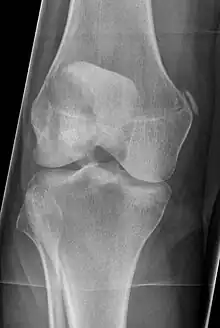

| Pellegrini-Stieda syndrome. Also visible is a fracture of the patella. |

Pellegrini–Stieda syndrome (also called Stieda disease and Köhler–Pellegrini–Stieda disease) refers to the ossification of the superior part of the medial collateral ligament of the knee. It is a common incidental finding on knee radiographs. It is named for the Italian surgeon A. Pellegrini (b. 1877) and the German surgeon A. Stieda (1869–1945).[1]